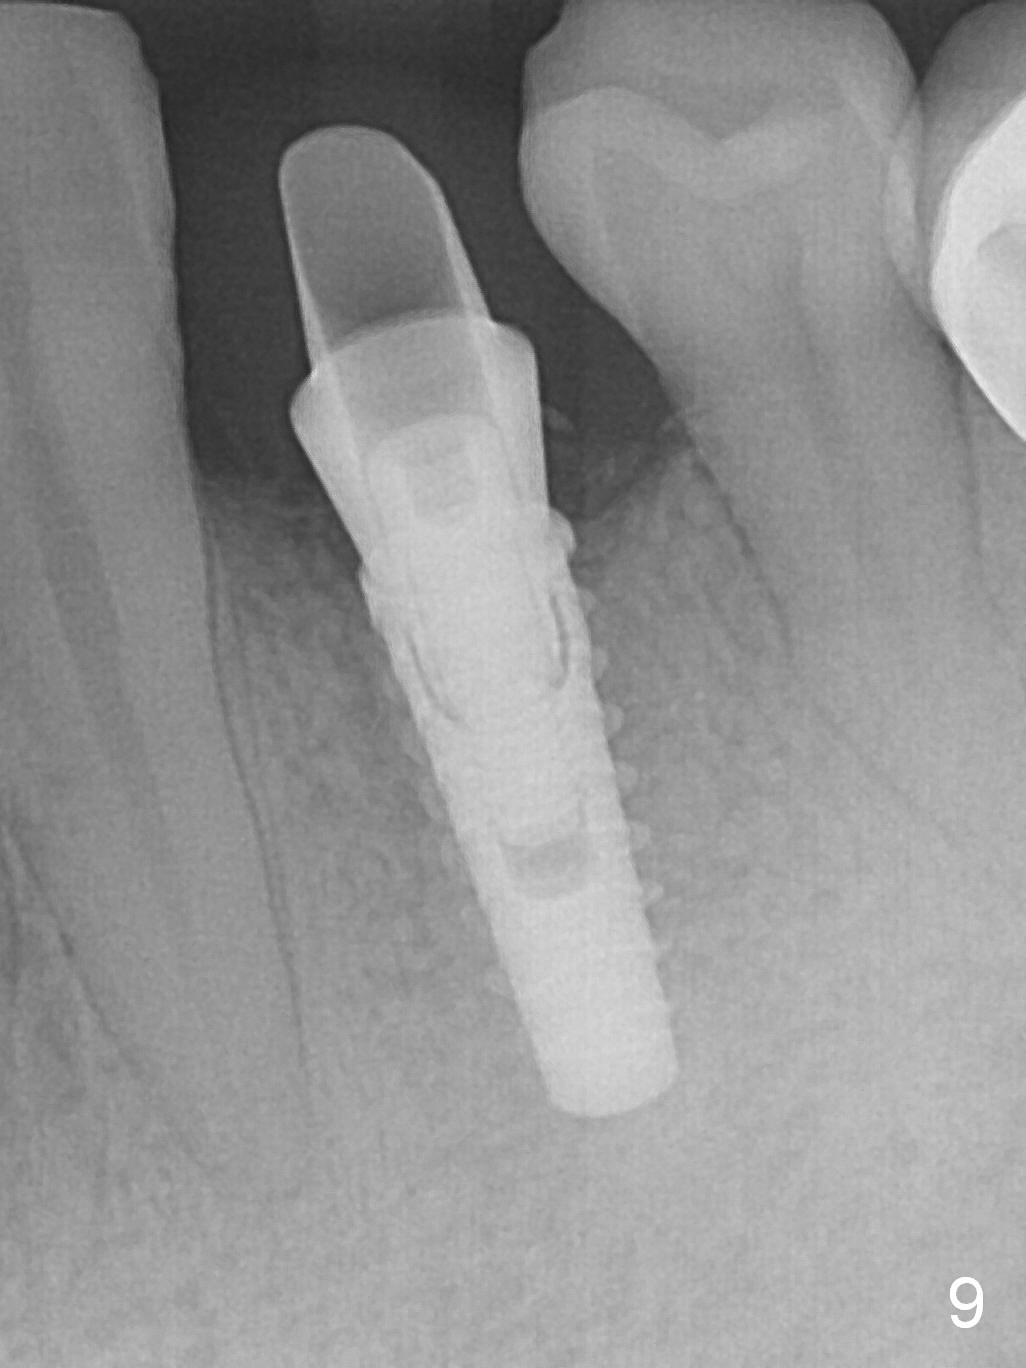

The implant seems to have osteointegrated 4 months postop (Fig.9).  When a permanent crown is fabricated, it should have normal occlusal and buccal contour (from Fig.11 (provisional) to 12 red and black curved lines) as well as the buccal cervical extension (Fig.12 to cover the buccal gingiva (Fig.10 *).  If the lingual margin of the abutment is too prominent, return the case and the abutment will be changed to the one with 2 mm cuff (existing 3 mm).  The lingual margin of the abutment will be trimmed.  The patient is not pleased with the short buccal margin of the crown after cementation (Fig.13).  In fact the provisional should have been fabricated so that the its buccal margin should be subgingival and within the gingival outline.  It may prevent buccal plate collapse.  In fact the crown dislodges 1 year post cementation.  The lingual margin is prep lower to increase the abutment height.  Impression is taken.  Although the access hole is unnecessary for cementation, it acts as an escape hole so that there is no excess cement cervically (Fig.14-18).